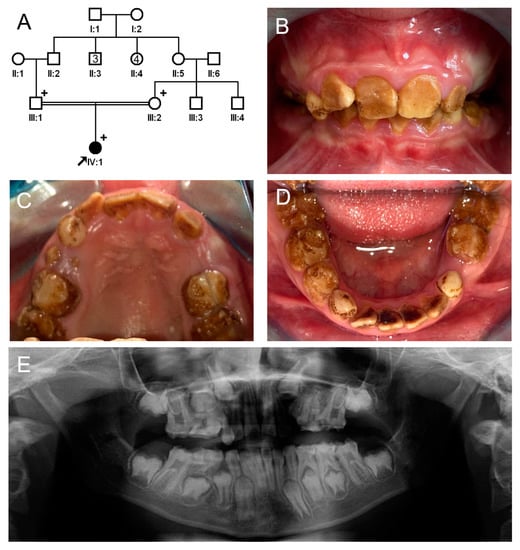

The proband of family 1 was a 12-year-old male, the fourth child from a consanguineous Turkish family (Figure 1). Pregnancy and delivery were uneventful, and he had no remarkable past medical history. His primary and permanent dentitions exhibited characteristic features of hypomaturation amelogenesis imperfecta: generalized yellow-brown discoloration, normal or near-normal thickness of enamel before tooth eruption, rapid dental attrition, or enamel fractures due to weak enamel. He also exhibited class II malocclusion with a deep overbite. There were no other family members with a similar dental phenotype. A recessive or de novo dominant mutation, therefore, was suspected.

Figure 1.

Pedigree, clinical photos, and panoramic radiograph of family 1. (A) Pedigree of family 1. The black symbol indicates the affected individual, and the proband is indicated by a black arrow. Plus signs above the symbols indicate participating individuals. The number inside the symbol indicates the number of siblings with the same gender. (B–D) Clinical photos of the proband at age 12 years. Maxillary central incisors have been treated with direct composite resin restorations. A newly erupted tooth (white arrow) exhibits a normal shape but discoloration before enamel fracture or attrition. Otherwise, all affected teeth show yellow-brown discoloration and enamel fractures and accelerated attritions. (E) Panoramic radiograph of the proband at age 12 years. Radiographically, unerupted teeth show normal crown shape with a reduced enamel radiodensity. Severe attrition and fractures can be seen in some teeth, especially in the first molars and deciduous second molars.